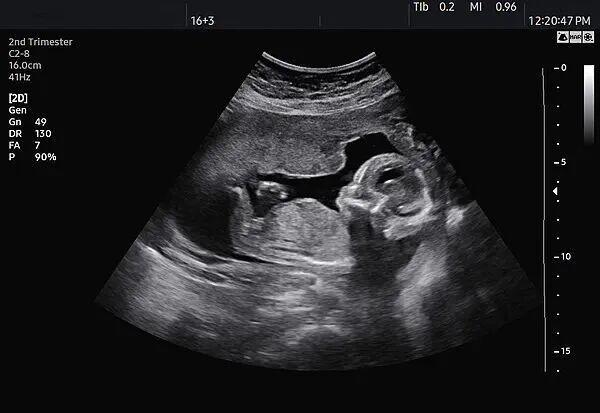

检察官找到了一名消费者,她表示通过某社交App加入了孕妇群,获悉该孕婴摄影店能为17周至34周孕妇提供拍摄婴儿照片的服务。她曾于2024年8月前往该店拍摄,店主用一台类似医院B超机的仪器为其拍摄宝宝动态影像,并暗示“宝宝很可爱,可以买粉色的衣服”。

与此同时,该店使用B超机的行为也可能涉嫌违法。《关于严禁非法使用超声诊断仪开展“胎儿摄影”活动的通知》规定,根据《医疗器械分类目录》规定,超声诊断仪属于第二类、第三类医疗器械,适用范围为医疗机构临床诊断。非医疗机构不得使用超声诊断仪。该店并非医疗机构,使用的超声诊断仪来源不明、质量不明,操作设备的工作人员是否有资质、操作是否规范同样不明,可能会对孕妇和胎儿的健康产生一定影响。